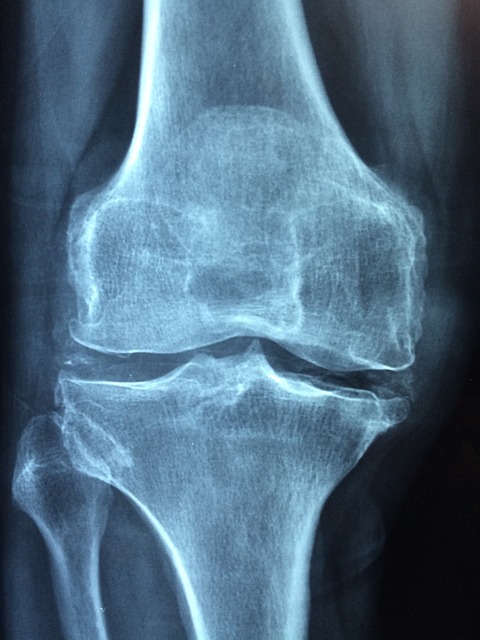

퇴행성 관절염이란?

퇴행성 관절염은 관절 연골이 점진적으로 손상되어 발생하는 가장 흔한 관절 질환입니다. 주로 나이가 들면서 관절 사용으로 인한 마모와 퇴행성 변화로 인해 발생합니다. 이 질환은 주로 무릎, 엉덩이, 손가락, 그리고 척추와 같은 부위에서 많이 나타납니다.

- 관절 통증: 관절을 움직일 때 통증이 발생하며, 움직이지 않을 때도 지속되는 경우가 많습니다. 초기에는 움직임 후에 통증이 나타나지만, 병이 진행됨에 따라 휴식 중에도 통증이 발생할 수 있습니다.

- 관절 경직: 관절이 뻣뻣해지고 움직임이 제한됩니다. 특히 아침에 심하게 나타나며, 몇 분에서 몇 시간까지 지속될 수 있습니다. 이로 인해 일상생활에서의 움직임이 어려워질 수 있습니다.

- 관절 부종: 관절 주변의 부종과 부기가 동반될 수 있습니다. 염증으로 인해 관절이 붓고, 붉어지며, 따뜻해질 수 있습니다.

- 관절 변형: 관절이 변형되어 기형이 생길 수 있습니다. 이로 인해 관절의 기능이 저하되고, 외형적인 변화가 발생할 수 있습니다.